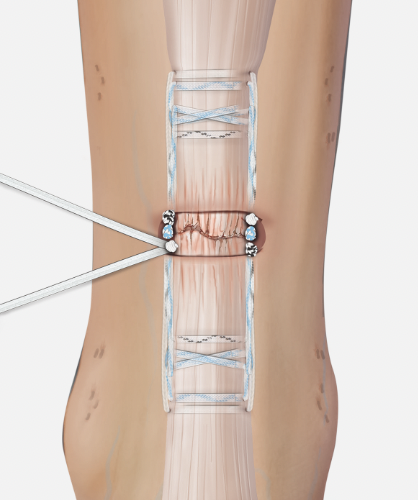

Open tendoachilles repair

Technique

Vumedi open achilles tendon repair

Prone position with tourniquet

- slightly medial incision to protect sural nerve

- full thickness skin flaps to paratenon

- identify and protect sural nerve

- divide paratenon longitudinally

- can incise paratenon in the midline anteriorly which increases tissue available for closure

- Bunnell Suture / Krackow suture x 2 with high strength suture / fibre wire

- one in proximal and one in distal tendon ends

- tie via two knots with foot fully plantar flexed

- +/- augment with circumferential 4.0 suture to minimize bunching

- careful closure of paratenon to prevent skin adhesions

- front slab in plantarflexion 2 weeks

- then standard accelerated rehabilitation

Anterior release of paratenon to allow posterior closure over achilles repair

Repair with proximal and distal Krackow high strength sutures